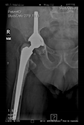

The direction of the cup stem was determined by the guide wire. The aiming device was needed to introduce this wire. After removing the aiming device, the next step was the drilling. Since a cannulated drill bit was used, the previously installed wire could guide the process. A self-positioning reaming tool was then used in the drilled channel. In the prepared cavity, the cup was fitted perfectly. Of the two stemmed cups available to us, the McMinn cup (Waldemar Link, Hamburg, Germany) had the simpler geometry and was therefore chosen. The stemmed cup was inserted according to the manufacturer’s recommendation. In the presence of a significant bone defect, a synthetic bone graft may be impacted for substitution.

The radiological examination allowed us to verify the close bone-to-implant contact and the unchanged position of the implant during follow-up.

In all the cases operated with the above-described targeting procedure, the stems of the cups remained between the cortical bone surfaces without perforation of the linea terminalis, as shown by postoperative radiographs. There were no complicated surgical situations. In 16 cases, the wound healings were uneventful, and the hips were able to bear weight again after postoperative rehabilitation.